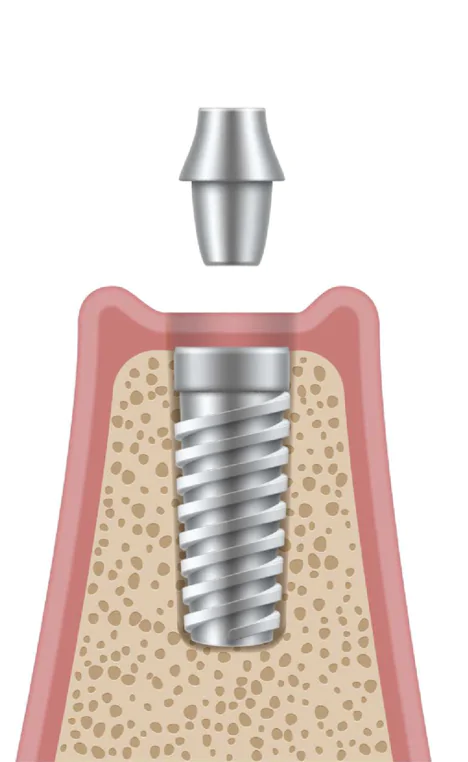

52次手術

1次手術で埋め込んだインプラント体が結合したことを確認できたら、その上部にアバットメントを装着するための2次手術に進みます。インプラント体は歯茎の下に埋まった状態であるため、まずは歯茎を切開して、頭の部分をあらわにします。そこに、歯肉の形を整える支柱を装着して、補綴処置開始まで1週間~2週間待ちます。

1次手術で埋め込んだインプラント体が結合したことを確認できたら、その上部にアバットメントを装着するための2次手術に進みます。インプラント体は歯茎の下に埋まった状態であるため、まずは歯茎を切開して、頭の部分をあらわにします。そこに、歯肉の形を整える支柱を装着して、補綴処置開始まで1週間~2週間待ちます。